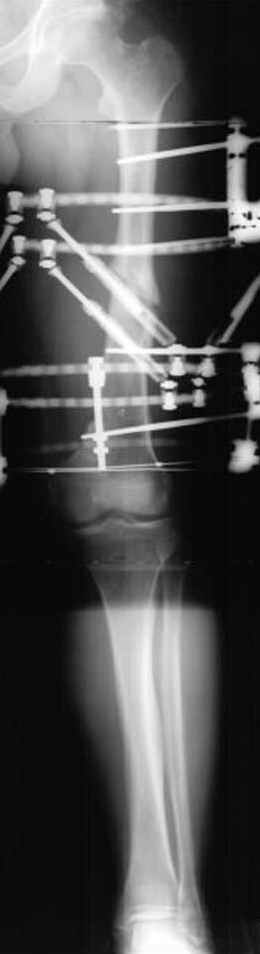

Djoldas Kuldjanov 23 Ноябрь 2004, 18:21

пластическая модель; и коррекция бедра аппаратом Илизарова.

• Re: Hip joint

Почему не замена гвоздя с рассверливанием, а аппарат?

Отправитель: Alexander Chelnokov 23 Ноябрь 2004, 21:29

Попробую угадать - была инфекция?

Отправитель: Evgueny Tschekashkin 24 Ноябрь 2004, 21:09

хотя даже если бы и инфекция , то nail exchange с рассверливанием канала - вариант дебрайдмента) Я думаю, что последовательность развития событий:

Узкий к-м канал - тонкий гвоздь- усталостный перелом дистальных винтов - развитие нестабильности и как ее результат остеолиз вокруг гвоздя - деформация анатомической оси бедра. Похоже, что я понял почему аппарат, а не новый гвоздь:-)

Отправитель: Alexander Chelnokov 24 Ноябрь 2004, 21:11

ET> хотя даже если бы и инфекция , то nail exchange с рассверливанием канала -

ET> вариант дебрайдмента)

Да, но если, скажем, течет из инфицированных каналов запирающих винтов, да инфекция в дистальном метафизе бедра - устанешь сверлить.

Аппарат в таком случае средство из серии "тише едешь - дальше будешь".

ET> Я думаю, что последовательность развития событий:

[...]

ET> деформация анатомической оси бедра.

Да, наверно. Но если ничего другого нету, ту небольшую деформацию можно было устранить дистрактором одномоментно ввести другой гвоздь.

ET> Похоже, что я понял почему аппарат, а не новый гвоздь:-)

Отправитель: Evgueny Tschekashkin 24 Ноябрь 2004, 21:13

> Да, но если, скажем, течет из инфицированных каналов запирающих винтов, да инфекция в дистальном метафизе бедра - устанешь сверлить.

ЕТ-Теоретически это возможно, а практически трудно представить - все-таки уровень медицинского сервиса высок, поэтому вряд ли инфекционное воспаление может зайти так далеко.....

> Тогда делись догадкой скорей!

ЕТ - Изначально костно-мозговой канал бедра был узкий, дальнейшее его рассверливание ещё больше скомпрометирует прочность бедра( латеральный кортекс дистального отломка уже истончен), приведет к дефекту наружной стенки - хотя это только мои догадки - хотелось бы знать мнение Джолдаса о выбранной тактике.